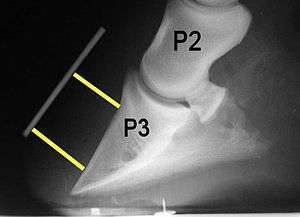

Radiographs

Radiographs are an important part of evaluating the laminitic horse. They not only allow the practitioner to determine the severity of the episode, which does not always correlate with degree of pain,[1] but also to gauge improvement and response to treatment. Several measurements are made to predict severity. Additionally, radiographs also allow the visualization and evaluation of the hoof capsule, and can help detect the presence of a lamellar wedge or seromas.[1] The lateral view provides the majority of the information regarding degree of rotation, sole depth, dorsal hoof wall thickness, and vertical deviation.[1][16] A 65-degree dorsopalmar view is useful in the case of chronic laminitis to evaluate the rim of the coffin bone for pathology.[1]

- Radiographic measurements

Several radiographic measurements, made on the lateral view, allow for objective evaluation of the episode.

- Horn:Lamellar Distance (HL): the measurement from the most superficial aspect of the dorsal hoof wall to the face of P3. 2 distances are compared: a proximal measurement made just distal to the extensor process of P3, and a distal measurement made toward the tip of P3. These two values should be similar. In cases of rotation, the distal measurement will be higher than the proximal. In cases of distal displacement, both values will increase, but may remain equal. Therefore, it is ideal to have baseline radiographs for horses, especially for those at high-risk for laminitis, to compare to should laminitis ever be suspected. Normal HL values vary by breed and age:[1]